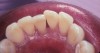

Fig 15. Diagnostic wax-up for porcelain veneers teeth Nos. 6 through 11.

Figure 15

Fig 16. VPS tooth preparation template fabricated on diagnostic wax-up cast. VPS template is cut with a scalpel at the incisal edges of the anterior teeth.

Figure 16

Fig 17. VPS reduction/preparation guide placed to evaluate the preparations needed for fabrication of the porcelain veneers for teeth Nos. 6 through 11.

Figure 17